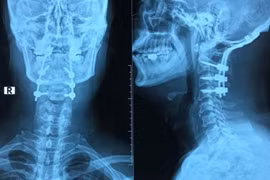

Gãy đốt sống cổ do nhảy ở bể bơi

(khoahocdoisong.vn) - BV TƯQĐ 108 tiếp nhận và điều trị cho bệnh nhân N.V.T, 55 tuổi (Hà Nội) nhập viện trong tình trạng chấn thương cột sống cổ, gãy đốt sống C1 do nhảy bể bơi, không để ý mực nước trong bể bơi còn bao nhiêu.